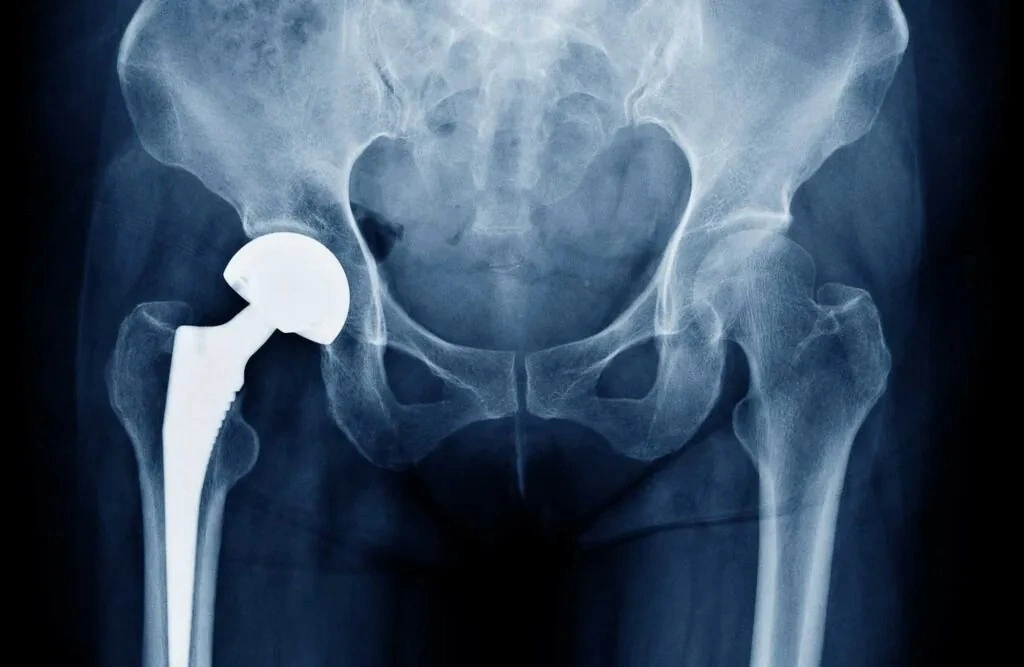

Hip replacement surgery is a medical procedure in which a damaged hip joint is replaced with an artificial implant. This implant is designed to replicate the function of a natural joint, allowing smooth movement and improved flexibility.

A prosthetic implant is placed into the hip socket and femur to replicate natural joint movement.

- Total Hip Replacement: Replacement of both the ball and socket of the joint.

- Partial Hip Replacement: Replacement of only one part of the joint.

- Revision Hip Replacement: Replacement of a previously implanted joint.